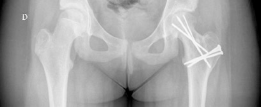

Comprehensive radiographic evaluation is mandatory. Standard imaging includes an anteroposterior view of the pelvis and a cross table lateral view of the affected hip. The frog leg lateral view is strictly contraindicated in unstable slips due to the risk of exacerbating the displacement and causing iatrogenic vascular injury.

Advanced imaging is heavily relied upon in contemporary practice. Magnetic Resonance Imaging is utilized to assess the pre operative perfusion status of the femoral head. T1 weighted and short tau inversion recovery sequences, often supplemented with gadolinium contrast, can identify pre existing ischemia. A pre operative diagnosis of avascular necrosis fundamentally alters the surgical discussion and prognosis. Computed Tomography with three dimensional reconstruction is occasionally utilized to quantify the exact degree of retroversion and the volume of the metaphyseal step off, aiding in the spatial conceptualization of the required osteotomy.

Once anatomical reduction is confirmed visually and fluoroscopically, temporary fixation is achieved with smooth Kirschner wires. Definitive fixation is typically accomplished using two or three fully threaded cannulated screws or specialized physeal implants. Fully threaded screws are preferred as they prevent compression across the osteotomy site, which could inadvertently tension the retinacular vessels. The screws must not penetrate the articular surface.